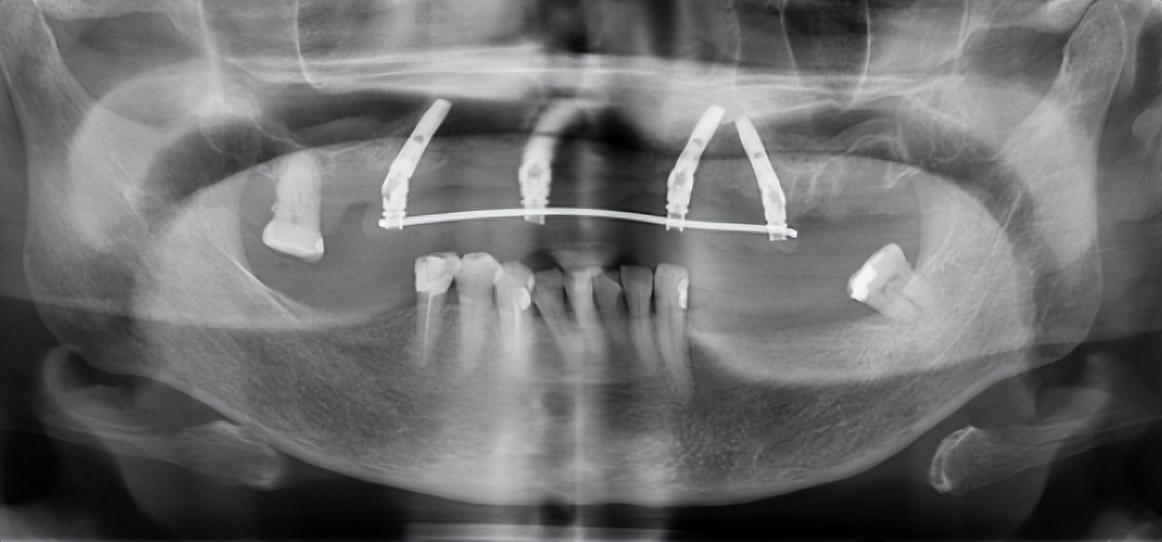

1、種植牙的醫(yī)療設(shè)備要求高,種來自植技術(shù)需要配備較高的設(shè)備環(huán)境,例如大型X線診斷設(shè)備、臨床手術(shù)設(shè)備、技工設(shè)備、手術(shù)支持設(shè)備以及在義齒制作時(shí)需要的一些獨(dú)特的較貴重的修復(fù)材料。這是影響上海種植牙價(jià)格的另一個(gè)因素。2、種植牙材料成本高決定了上海種植牙價(jià)格,種植體的加工工藝復(fù)雜且要求極其。目前,世界上較著名的種植系統(tǒng),例如瑞典NOBEL種植系統(tǒng),種植體于滿足不同的修復(fù)設(shè)計(jì)需要,所以上海種植牙價(jià)格高。

目前,公立醫(yī)療機(jī)構(gòu)采購高端品牌種植體價(jià)格區(qū)間在每套4000元至6000元,其他種植體每套2000元至3500元,流通過程仍存在價(jià)格虛高空間,集采后價(jià)格將有不同程度下降。

口腔種植的費(fèi)用大致分為種植體、牙冠和醫(yī)療服務(wù)三個(gè)部分,相比耗材,降低種植牙醫(yī)療服務(wù)價(jià)格,難度要大得多,一些公立醫(yī)院種植牙醫(yī)療服務(wù)部分的平均費(fèi)用超過6000元,一些省市甚至超過9000元。此前,醫(yī)保局開展口腔種植收費(fèi)和醫(yī)療服務(wù)價(jià)格調(diào)查登記,初步結(jié)果顯示,醫(yī)療服務(wù)部分的費(fèi)用高是種牙貴的重要原因之一。

綜合患者、醫(yī)療機(jī)構(gòu)等多方意見后,三級公立醫(yī)院單顆常規(guī)種植的醫(yī)療服務(wù)價(jià)格調(diào)控目標(biāo)確定為4500元,包括門診診查、生化檢驗(yàn)和影像檢查、種植體植入、牙冠置入等費(fèi)用,但不含種植體和牙冠的費(fèi)用。